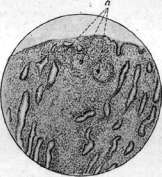

Pnc, 1. Милиарпын the легкого; значительный отек ткани легкого. Рис, 2. ЗажквшнЯ первичный аффект {через луну): а-^костные балки с участками костного мозга (с) между ними; d—творожистые МАССЫ; Ь—фиброзная i;;ui-Сула, отграничивающая аффект. Рисунок 3, Заживший первичный аффект (через лупу). Рисунок А. Туб. бугорки (а) в слизистой оболочке .матиц. Гпс. 5. Линзы Коха на стенке каверны и легком. I'hc. 6. Солитарпый tbc селезенки. Рисунок 7. Заживший первичный аффект нижней доли правого легкого у старика-шфизематпка (видно пузыревидное вздутие передник н верхних ч а стен легкого); аффект имеет вид окостеневшего образовании, лежит тотчас под утолщенной плеврой.